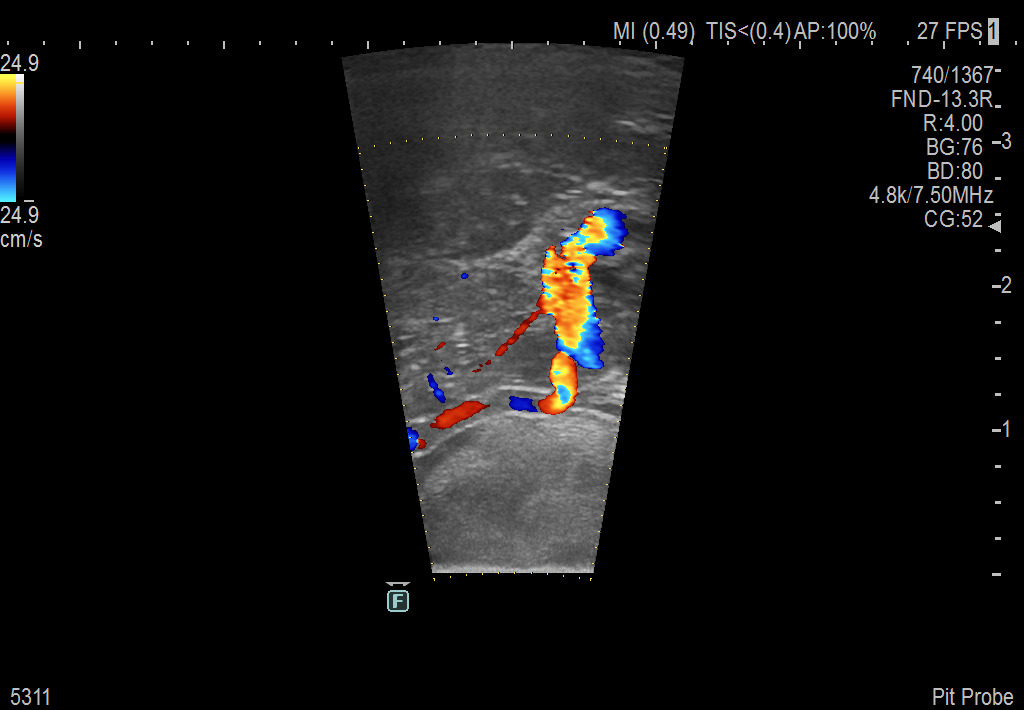

Exclusive 10mm side-fire linear array transducer with 2.87mm diameter is ideal for real-time visualization through and behind structures and instant, scalable definition of anatomy and vascularity including the ability to delineate and define tumor margins.